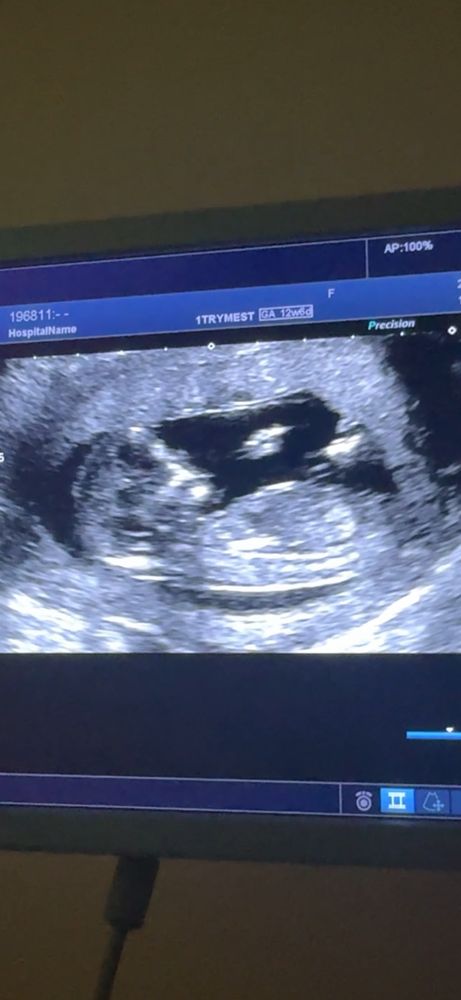

Пол ребенка 1 скрининг

Девочка , угол маленький между спинкой и половым бугорком , почти параллельны. При мальчике большой угол

Девочка, половой бугорок параллельно спинке